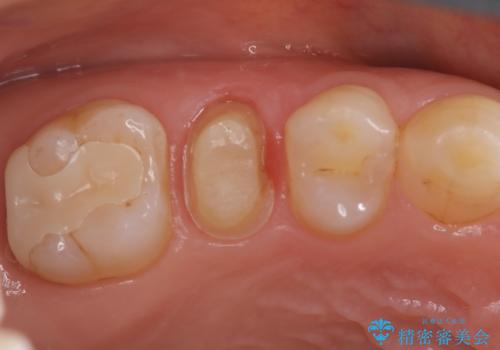

【オールセラミッククラウン】根管治療も行いたい。

- 右上の歯が、噛むと痛いことを主訴に来院されました。

ラバーダムと顕微鏡を用いた根管治療を希望され、治療後は痛みも改善することができました。

その後、オールセラミッククラウンにて修復を行っています。

顕微鏡を用いて根管治療を行うことで、破折の有無などを判断しやすくなります。